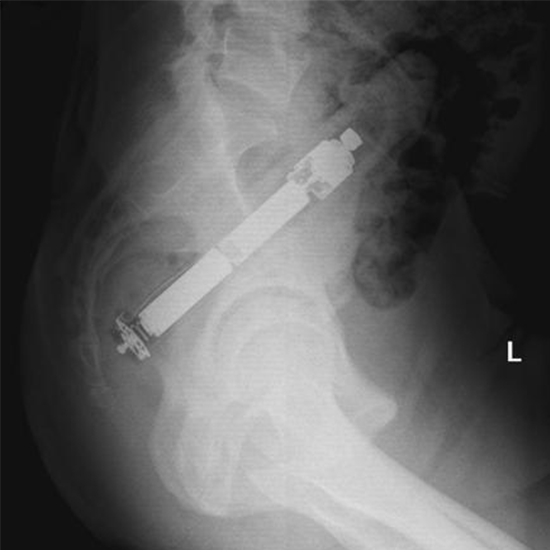

X-Ray Abdomen Lateral View

X-Ray Abdomen the Lateral View test is used to see the organs in the abdomen, such as the stomach, intestines, gallbladder, base of the lungs, liver, and spleen. The frontal view of the abdomen is helped by an X-ray taken from the side.